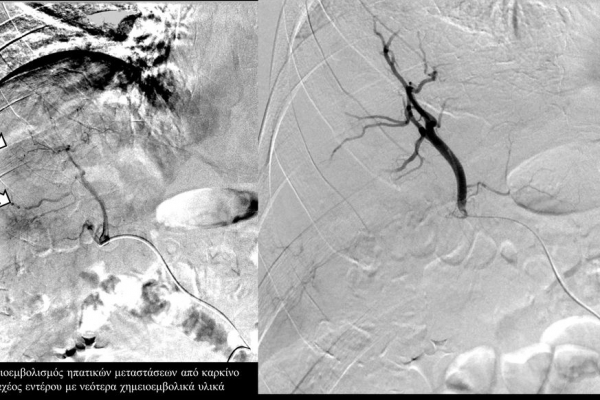

Ενδείκνυται επίσης σε ηπατικές μεταστάσεις από νευροενδοκρινείς όγκους, καρκίνο παχέος εντέρου και μελάνωμα, σε συνδυασμό με συστηματική χημειοθεραπεία της οποίας ενισχύει και βελτιώνει τα αποτελέσματα.